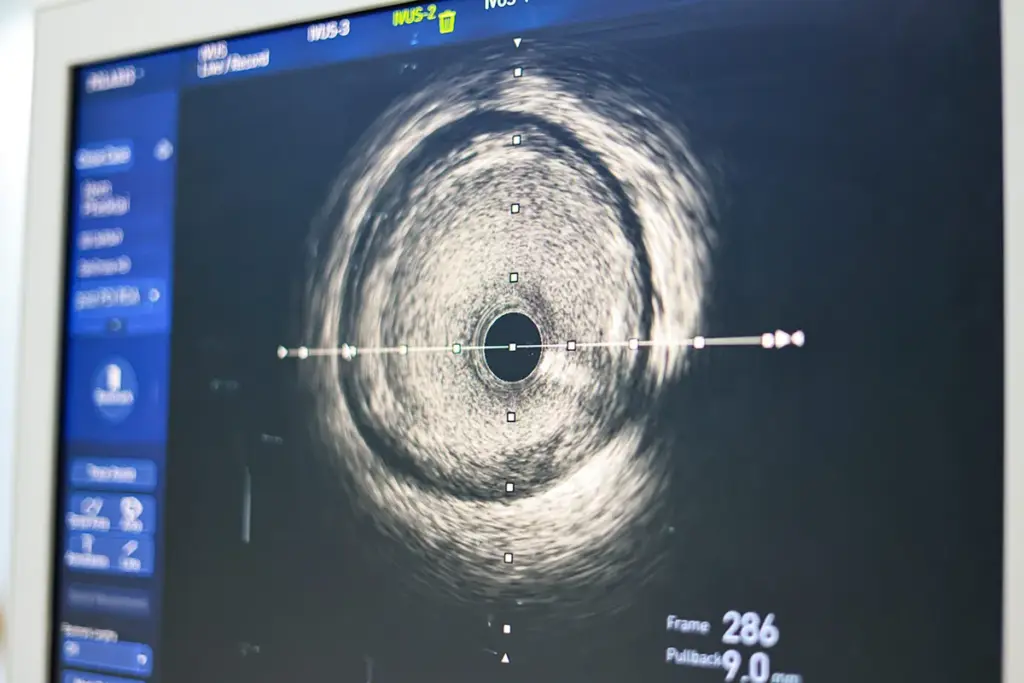

Intravascular Ultrasound (IVUS) |

Real-time imaging inside blood vessels |

Enhanced diagnostic accuracy |

Specialized Catheterization Techniques

There are special catheterization techniques for certain needs. These include fractional flow reserve (FFR) and intravascular ultrasound (IVUS). They help in detailed coronary artery imaging.

- Intravascular Ultrasound (IVUS): Offers detailed images of the artery walls.

Intravascular Ultrasound (IVUS)

Intravascular ultrasound (IVUS) is a detailed imaging method. It uses a small probe to see inside the arteries. This helps doctors see how much plaque there is and plan treatments.

Image coronary artery walls |

Assesses plaque buildup and guides interventions |